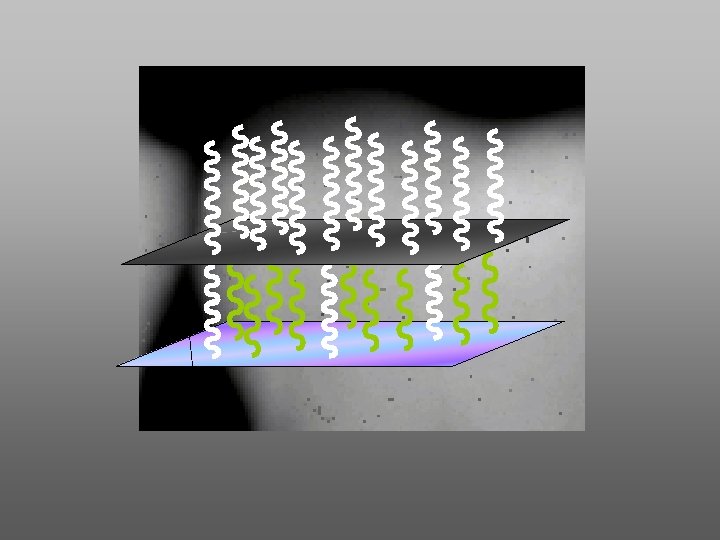

SISTEMA INDIRECTO 0 ESCANEADO 1. 3 EMISOR DE RAYOS “X” CONVENCIONAL 2. PLACA DE FOSFORO 5 3. ESCANER DE PLACAS DE FOSFORO (láser de helioneón) 4. SOFTWARE (DICOM) 2 5. MONITOR 1 6 6. IMPRESORA

Componentes del sistema indirecto a. - Placas de fósforo y barreras b. - Escáners de placas de fósforo c. - Borrador de placas de fósforo (luz blanca)